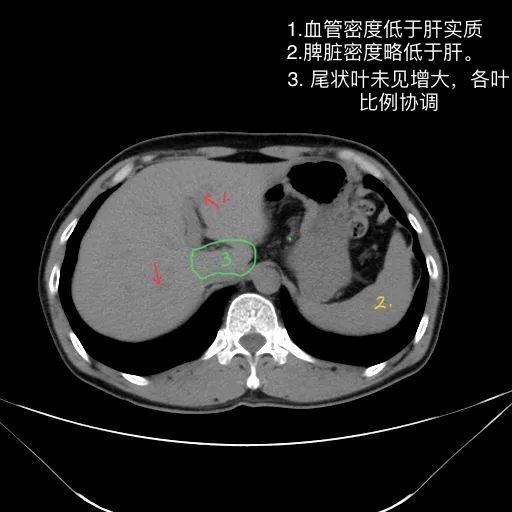

肝脏形态、密度、大小未见异常,各叶比例协调,包膜光滑,肝实质未见明确异常密度影;胆道未见扩张;胆囊形态、大小未见异常,胆囊壁光滑,其内未见异常密度影;胰腺、脾脏形态、密度、大小未见异常;双肾上腺及双肾形态、密度、大小未见异常,双输尿管未见扩张,膀胱充盈良好,壁光滑,其内未见异常密度影;前列腺/子宫及附件未见异常;胃肠道未见充盈,壁未见明确增厚;腹部及腹膜后未见肿大淋巴结。

1.肝脏、胆囊、胰腺、脾脏CT平扫未见异常。

肝脏缩小,包膜凹凸不平,肝裂增宽,各叶比例失衡,肝实质密度不均,肝S4小片低密度影,约cm;胆囊不大,其内未见异常密度影,胆道系统未见扩张;胰腺、脾脏形态、密度、大小未见异常;双肾上腺及双肾形态、密度、大小未见异常,双输尿管未见扩张,膀胱充盈良好,壁光滑,其内未见异常密度影;前列腺未见异常;胃肠道未见充盈,壁未见明确增厚,食管胃底多发迂曲、增粗血管,腹部及腹膜后未见肿大淋巴结;腹水。

1.肝硬化失代偿表现(腹水,食管胃底静脉曲张)。